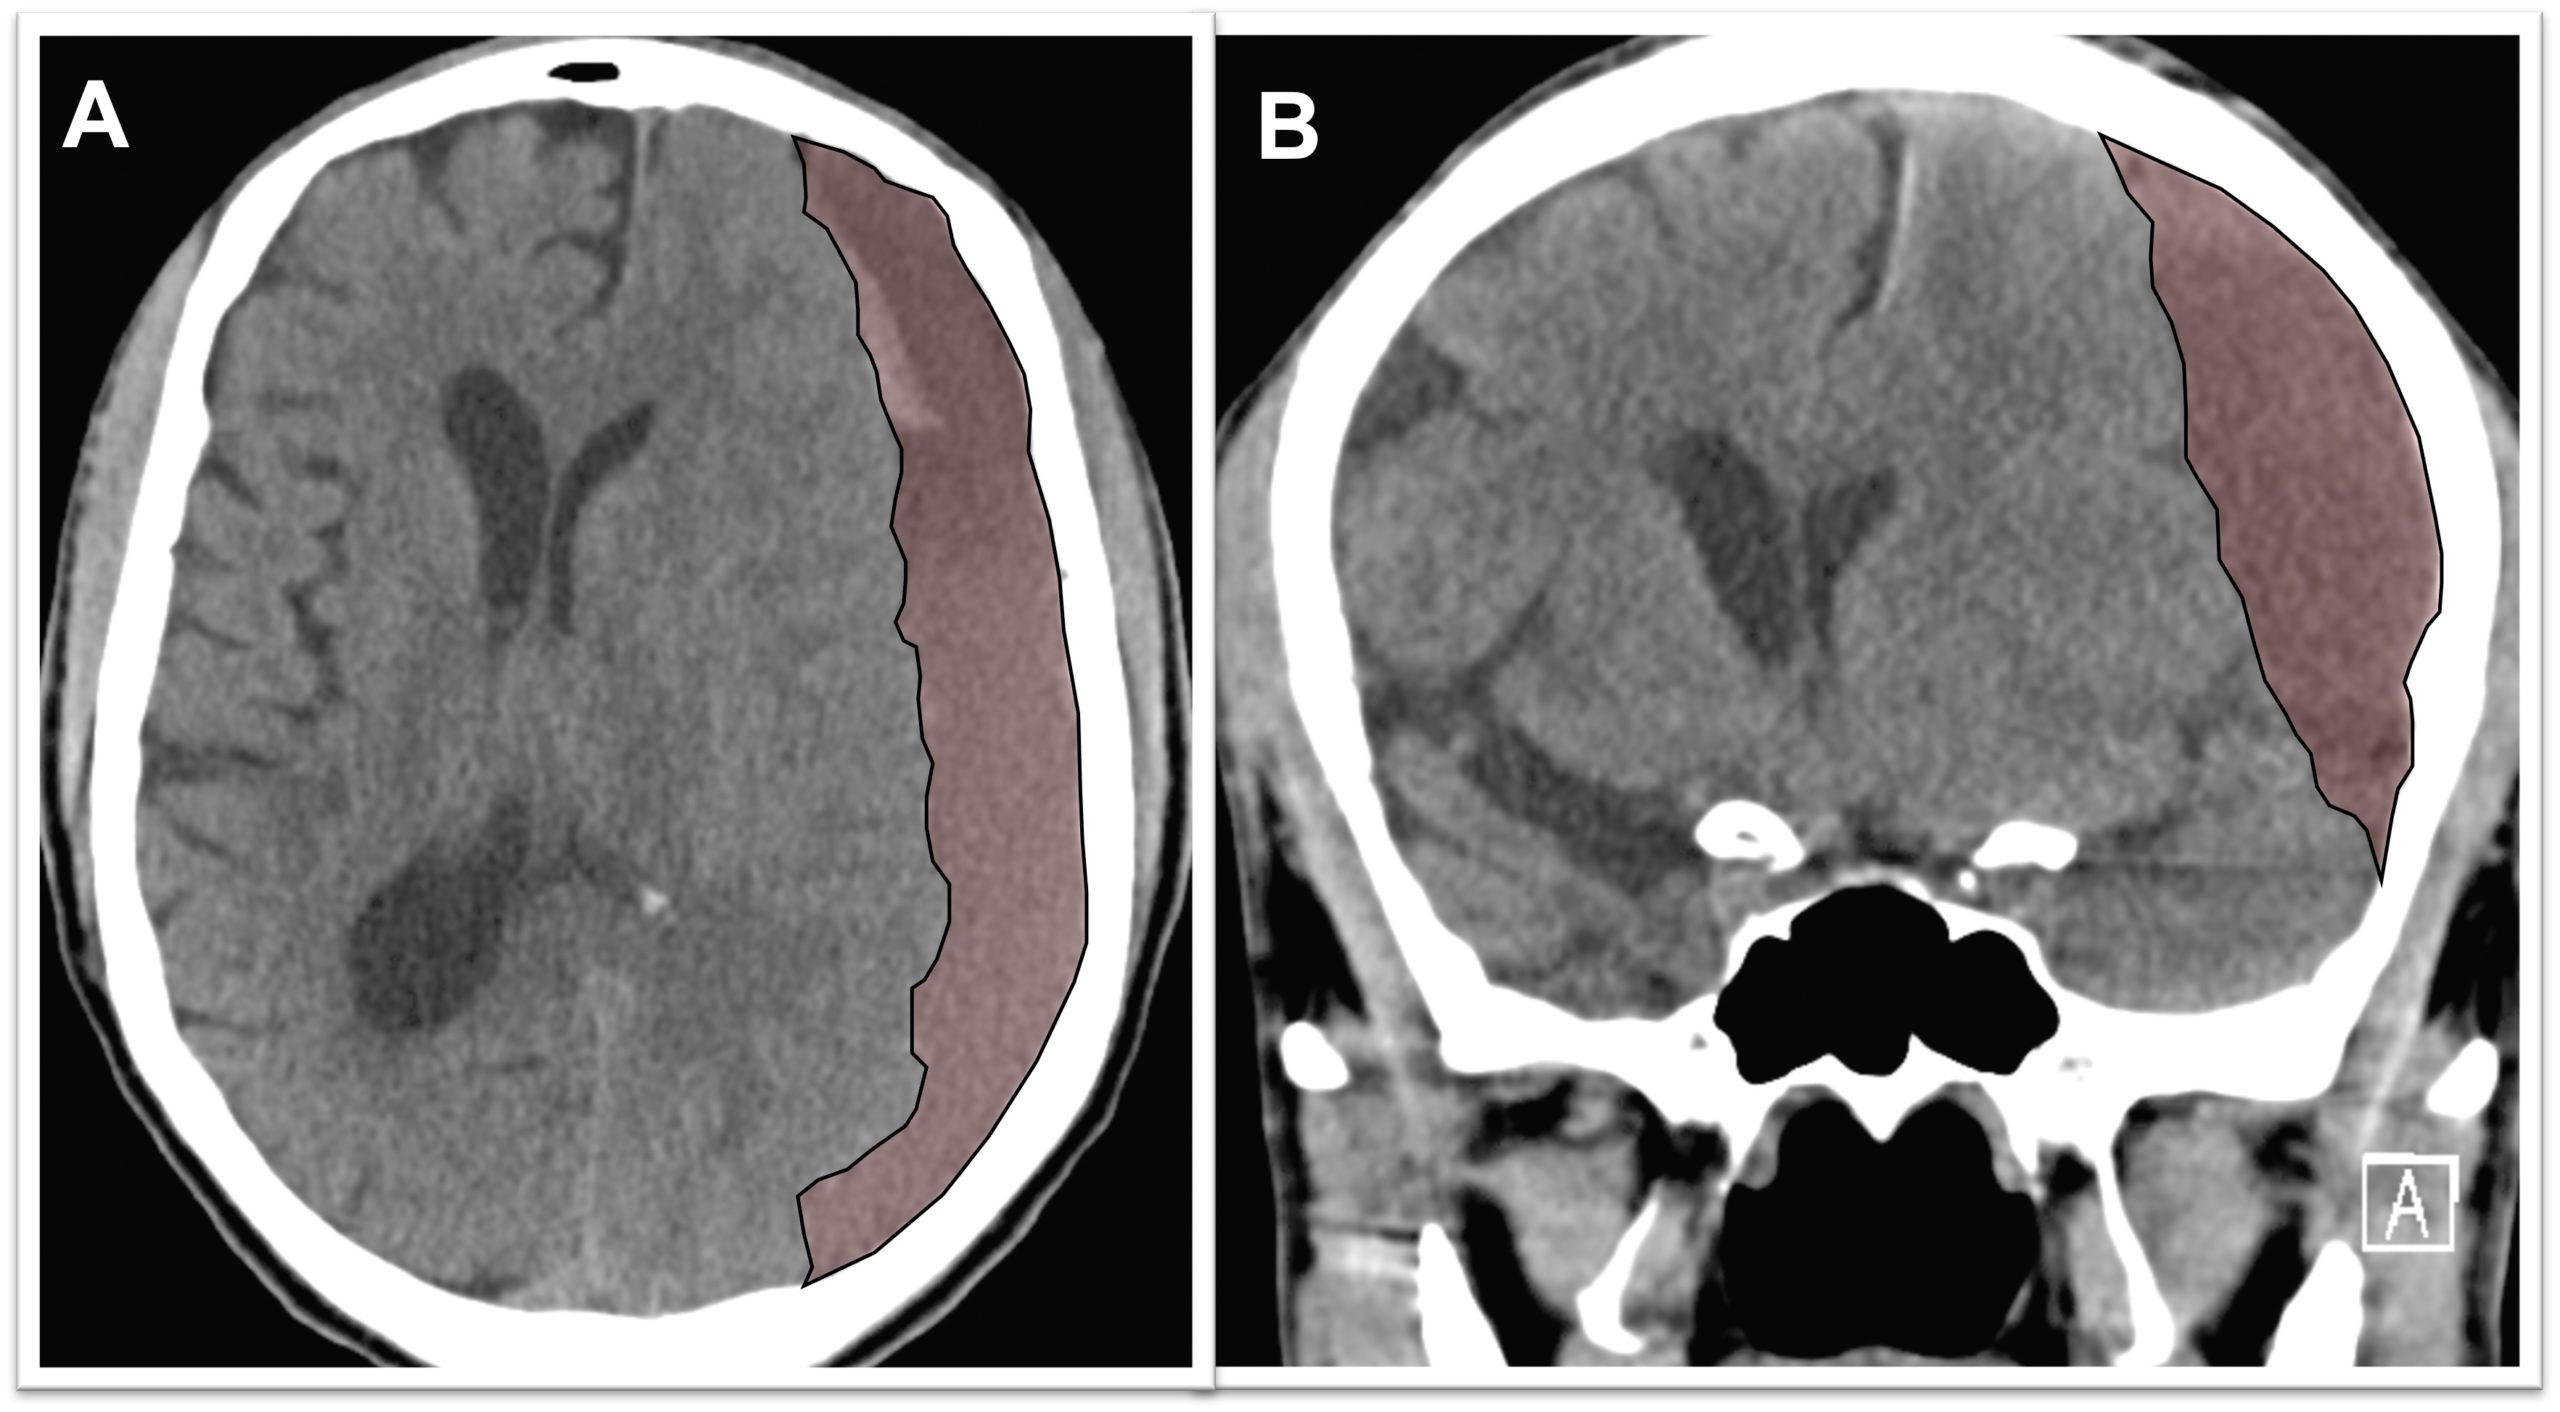

Chronic subdural hematoma (cSDH) is an abnormal collection of blood products in the fluid space between the surface of the brain and the inner lining of the skull, called the “dura matter.” These types of blood product collections occur more frequently in older age groups due to the increased space between the brain surface and the dura matter. Read more…